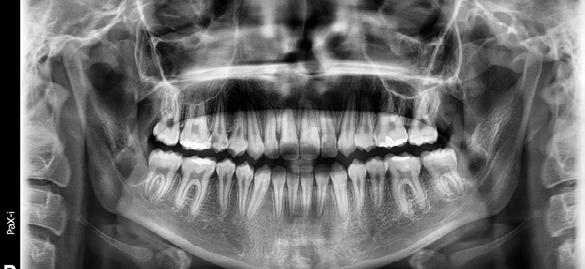

En la radiografía lateral de cráneo ( Figura 5 ) se observa la clase II esquelética con un ANB de 5°, hiperdivergencia, con la retroinclinación del incisivo superior con 1 a plano palatino de 111° y proinclinado el incisivo inferior de 1 a plano mandibular de 101°.

En la radiografía panorámica (Figura 6) se ven 32 dientes, con los terceros molares en formación.

Figura 3. Oclusal superior. Figura 4. Derecha, izquierda. Figura 5. Izquierda inicio. Figura 6. Radiografía lateral de cráneo y radiografía panorámica.